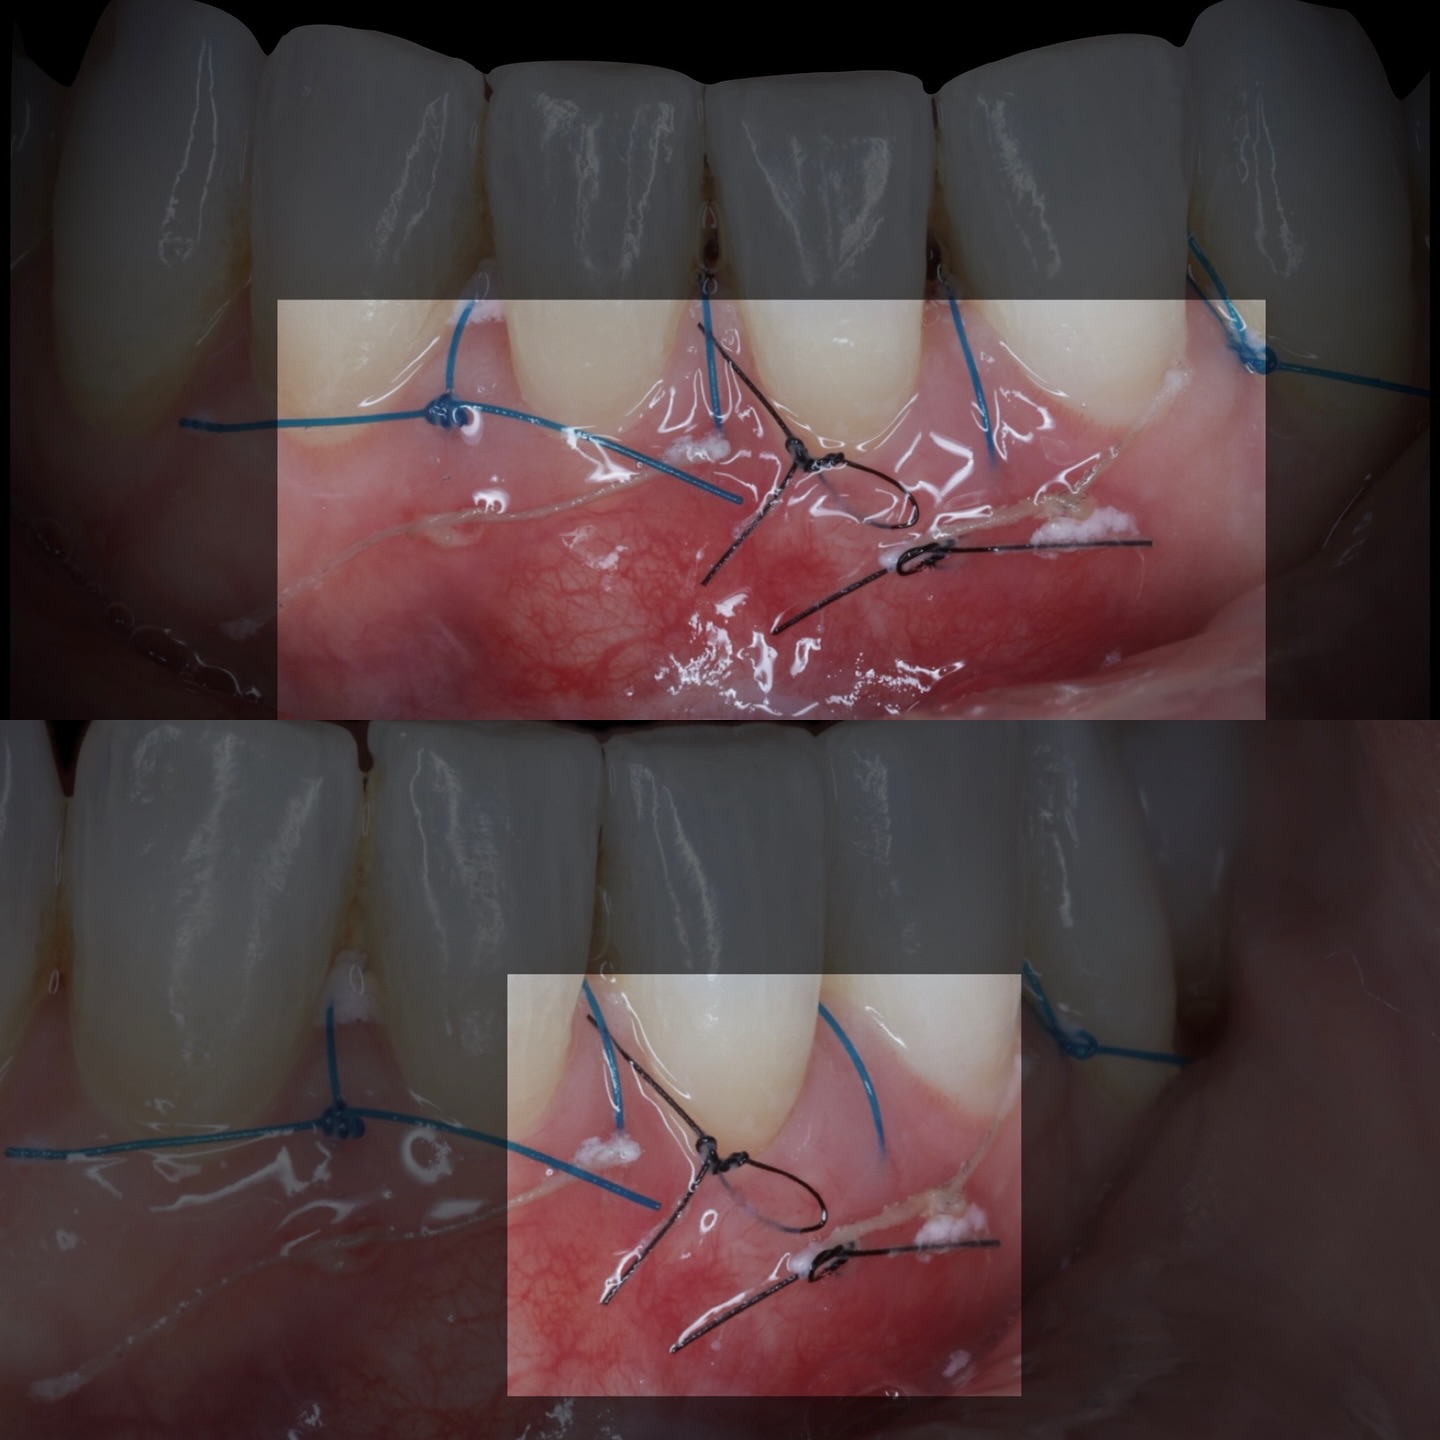

Durante una mañana, asistirás a una Cirugía Mucogingival de recubrimiento radicular de recesiones múltiples en IV y V sextante (36 a 43).

Gracias al uso del microscopio y a la proyección en tiempo real en pantalla, verás exactamente lo mismo que veo yo durante la cirugía, sin tener que estar

Podrás asistir a la planificación de casos y cirugía de injerto de tejido conectivo. Factores determinantes y elección de la técnica adecuada. Sumérgete en un protocolo predecible y técnicamente correcto para obtener resultados óptimos.

Se realizará todo el procedimiento con un microscopio operatorio, lo que permite al alumno ver toda la cirugía en directo en una pantalla en la sala de cirugía.

Aprende la planificación y técnica de la cirugía Mucogingival para el recubrimiento de recesiones y aumento de banda queratinizada en el sector anteroinferior

La formación comenzará con la presentación del caso clínico que se abordará durante el curso, seguida de una cirugía en directo, que permitirá observar paso a paso el procedimiento y la toma de decisiones clínicas. Durante la jornada se profundizará en los conceptos biológicos aplicados a

Una estancia clínica pensada para quienes quieran iniciarse o dar un paso más en el campo de la cirugía mucogingival. Durante esta experiencia tendrás la oportunidad de aprender en directo cómo se planifica y se lleva a cabo una cirugía mucogingival mediante técnica de Túnel.

Formación teórico-práctica completa sobre las técnicas más avanzadas en cirugía mucogingival. Durante dos días intensivos, los participantes aprenderán desde la evidencia científica y la anatomía de las zonas donantes hasta la ejecución de injertos, cubrimiento radicular y aumento de